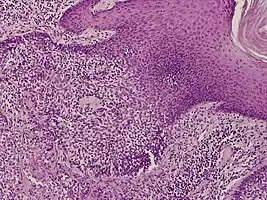

Histology

They are described as < 1 to 2 cm, pink/red shiny, exophytic lesions that can be pigmented and are clinically very similar to pyogenic granulomas.[3] Histologically, the cells as PAS-positive and clearly surrounded by normal keratinocytes. These tumors are surgically excised usually without complication or recurrence, although malignant porocarcinomas can recur and metastasize to local lymph nodes.[5]

Dermoscopy and histopathology of eccrine poroma: (A) Clinical presentation of a nonpigmented eccrine poroma sensu stricto as a pink nodule located on the foot (B,C) Dermoscopy shows milky red areas (light blue arrow), milky red globules (dark blue triangle), and dotted vessels (black arrow) (original magnifications ×20 and ×40, respectively). (D,E) Histopathologically, the neoplasm consists of poroid and cuticular cells and tubular structures that are continuous with the epidermis (H&E stain, original magnifications ×10 and ×40, respectively).[6]